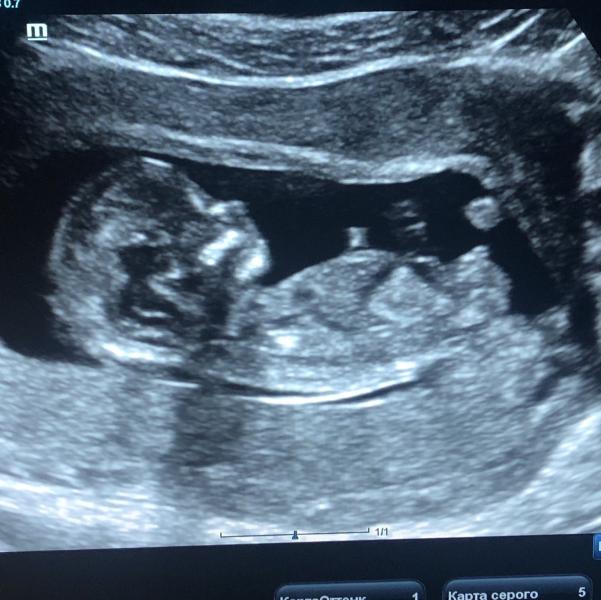

у нас сегодня первый скрининг был. так эмоционально) хорошо что всё хорошо

@ta_verusya, просто очень четкая картинка ) делала тоже во второй но такого четкого кадра не было)

Я на вашем сроке ,на первом скрининге,у врача спросила :"А что это за палочка?",она мне:"Могу предположить - мальчик👶,но не точно". И не ошиблась. Вероятно и у вас мальчик.Поздравляю👶❤👋🌷